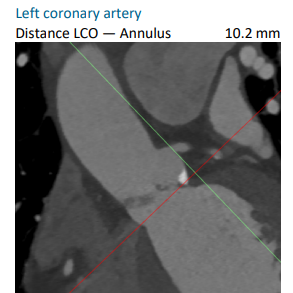

FEops评估冠脉风险

根据FEops报告上的左右冠脉CT截面得知RCA Height:12.9mm、LCA Height:10.2mm,具有一定冠脉闭塞风险,通过观察模拟植入后瓣叶与冠脉开口的位置关系,建议术中进行球囊扩张进一步评估情况,确保手术安全。